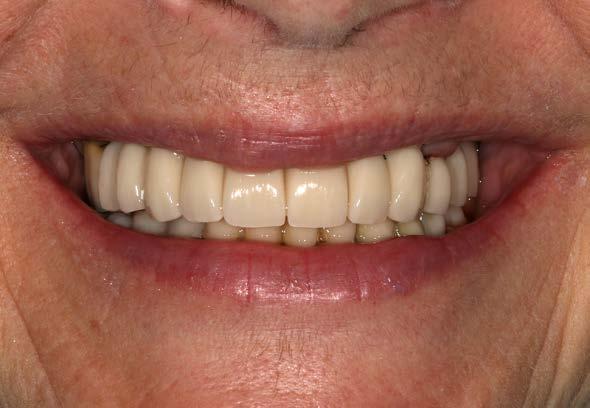

Figura 7 y 8. Fotografías de la prótesis de carga inmediata. En ellas observamos ambas prótesis (superior e inferior) colocadas horas después de la cirugía.

190. Junio 2024 17

Figuras 10 y 11. Caso finalizado 6 meses después, con las prótesis definitivas colocadas.

190.

2024 19

Junio